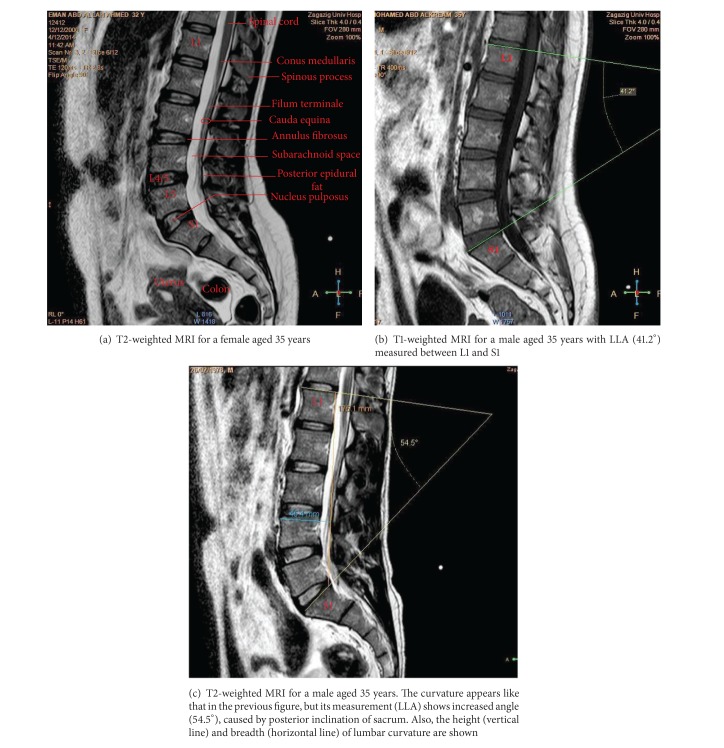

尽管人们越来越认识到腰椎前凸的功能和临床重要性,但对其描述知之甚少,特别是在埃及。与此同时,磁共振成像(MRI)作为一种无创诊断技术已被引入。本研究的目的是利用正中矢状位核磁共振检查腰椎前凸的解剖结构。93例正常腰椎mri(男性46例,女性47例;25-57岁)进行回顾性评价。腰椎曲度及其节段“椎骨和椎间盘”被描述和测量。女性腰椎前凸角(LLA)大于男性。其平均值随年龄增长而增加。男性腰高(LH)高于女性。同时,女性腰宽(LB)高于男性。腰椎指数(LI = LB/LH × 100)性别差异有统计学意义(P < 0.0001)。腰椎前凸是由下腰椎的椎间盘和椎体楔入形成的。总之,MRI可以清楚地显示腰椎前凸的解剖结构。结合LLA使用LI可用于评估腰椎前凸。

Despite the increasing recognition of the functional and clinical importance of lumbar lordosis, little is known about its description, particularly in Egypt. At the same time, magnetic resonance imaging (MRI) has been introduced as a noninvasive diagnostic technique. The aim of this study was to investigate the anatomy of the lumbar lordosis using midsagittal MRIs. Normal lumbar spine MRIs obtained from 93 individuals (46 males, 47 females; 25-57 years old) were evaluated retrospectively. The lumbar spine curvature and its segments "vertebrae and discs" were described and measured. The lumbar lordosis angle (LLA) was larger in females than in males. Its mean values increased by age. The lumbar height (LH) was longer in males than in females. At the same time, the lumbar breadth (LB) was higher in females than in males. Lumbar index (LI = LB/LH × 100) showed significant gender differences (P < 0.0001). Lordosis was formed by wedging of intervertebral discs and bodies of lower lumbar vertebrae. In conclusion, MRI might clearly reveal the anatomy of the lumbar lordosis. Use of LI in association with LLA could be useful in evaluation of lumbar lordosis.